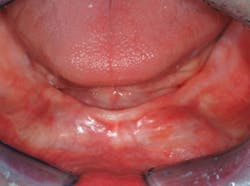

Q Two devices have me confused. Some of my dentist friends are enthused about cutting tooth structure with aluminum oxide expelled from an air-abrasion unit. Others with whom I have spoken are using sodium bicarbonate in an air-slurry polisher. I have not used either of the devices. Do both of them cut tooth structure? If so, which is the best for minimal tooth preparations? Can staff members legally use these devices?A Although both of these concepts are highly useful for various aspects of oral therapy, neither of them are very popular in practice. In my opinion, both should be used more in general and pediatric practices. I will answer your questions and discuss the numerous advantages and disadvantages of each type of device.Air-slurry polishers are extremely valuable for numerous clinical procedures. It remains a mystery to me why more dentists do not use them. The following information will describe the concept and explain the uses (Fig. 1).

Fig. 1 — The Cavitron® Jet Plus™ from DENTSPLY combines the Cavitron magnetostrictive ultrasonic scaler and an air-slurry polisher in one compact unit. Most users of this device find it easy to use and reliable.